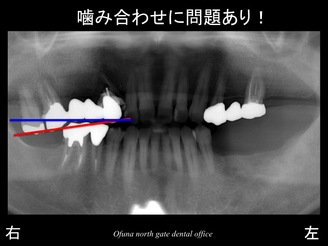

また 診査の結果、さまざまな問題が起こっていました。

その一つが、噛み合わせのズレです。

下顎の右側の奥歯が欠損した状態で長期間放置してしまったため、

噛み合う上顎の歯が挺出してきたのです。

以下のレントゲンは、噛み合わせのズレを表示したものです。

青線は、正常な状態を表した状態です。

以下の赤線は、現在の患者様の状態です。

上顎の歯が挺出し、噛み合わせが斜めになっているのが分かるかと思います。

青線赤線を合わせたのが以下の写真です。